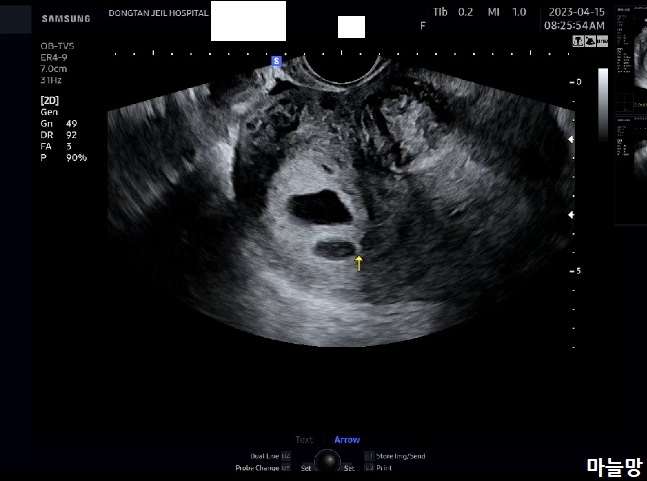

그리고, 질초음파를 봅니다.

「아기집 괜찮고요」가 먼저 들려왔어요.

그리고 보인 초음파 화면의 아기집은 붉은 피 출혈에도 쓸려 내려가지 않고 자리를 지키고 있었습니다.

그 후에, 「여기 아기집이 하나 더 보이네요」라고 말씀해 주셨어요.

그러면서 후둥이는 나중에 생겨서 도태될 수 있다고 사이즈가 작아서 조금 더 지켜봐야 한다고 하셨어요.

붉은 피가 후둥이 쪽에서 나온 것일 수도 있다는 의사쌤 말씀과 함께 6주 2일 차의 한참 작은 아기들의 심장소리도 들려주셨어요. 아직 아기들 주수가 작아서 심장소리는 마치 잘못 맞춰놓은 라디오 주파수 같았어요.

선둥이는 심장 깜박임이 초음파 화면상으로도 선명하게 보였어요.

후둥이는 아직 너무 작아서 초음파 상으로도 심장소리 잡고 놓치고를 반복...!

오늘의 초음파 사진은 마미톡 캡처사진입니다.